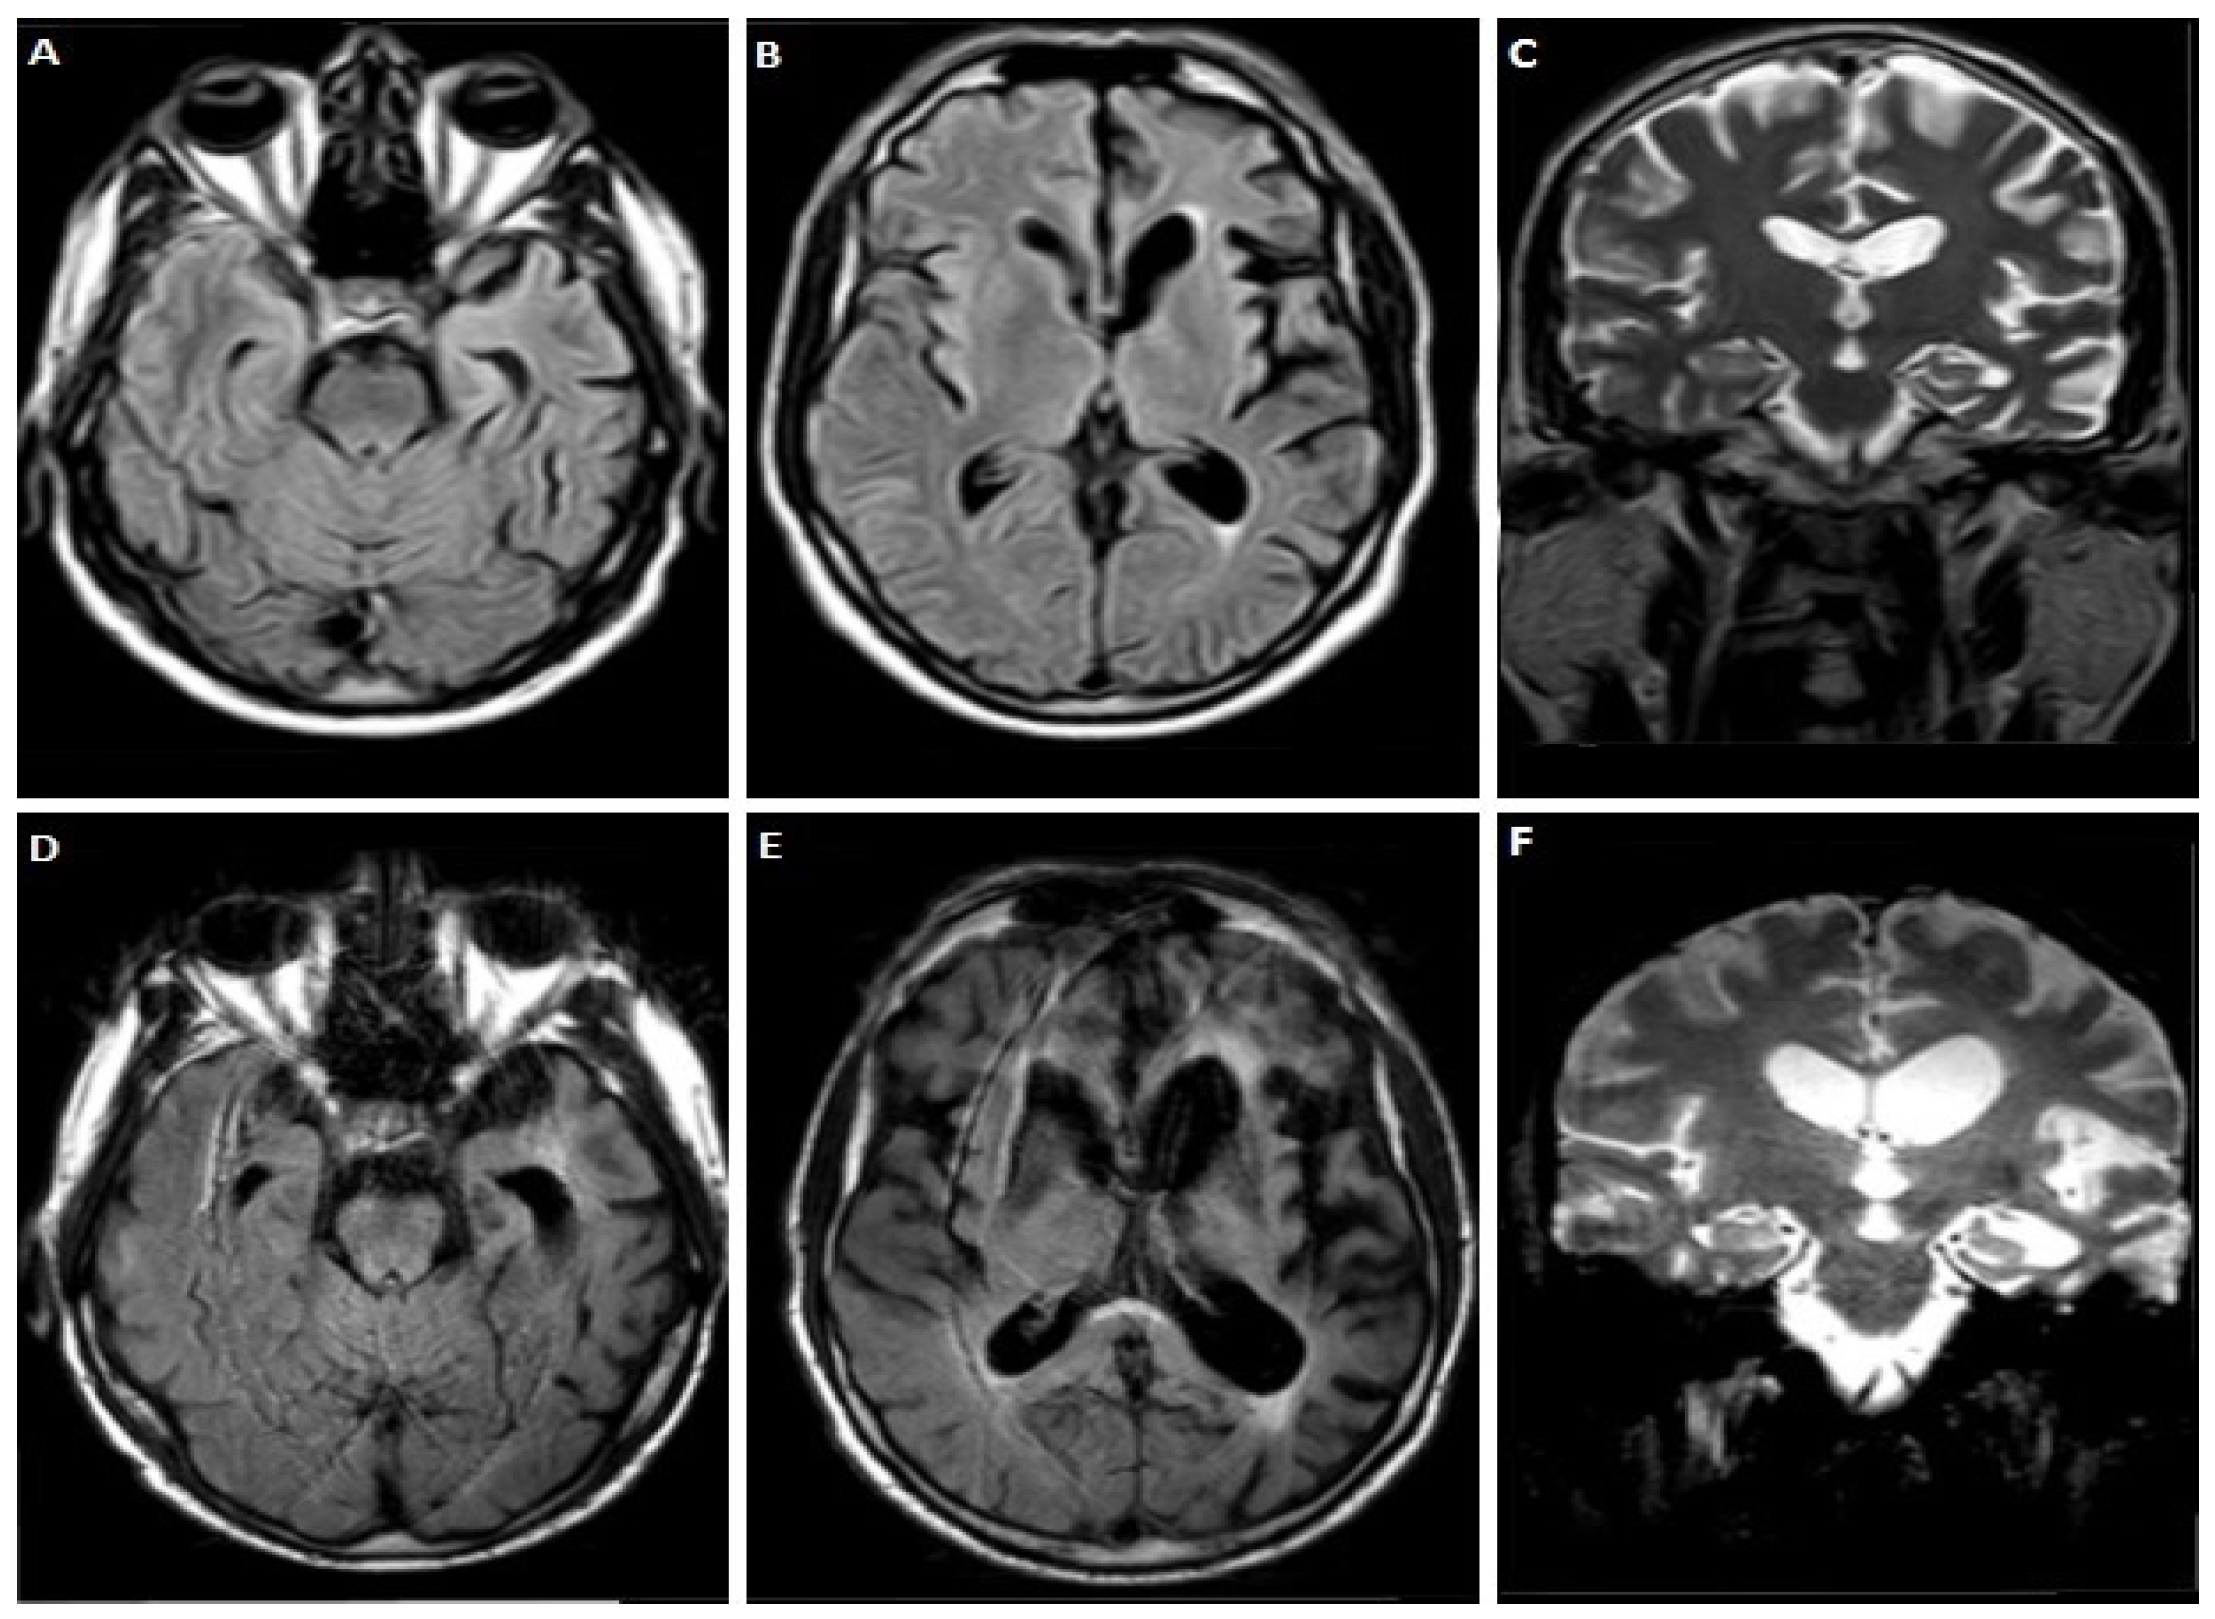

3.1.2. Case 2